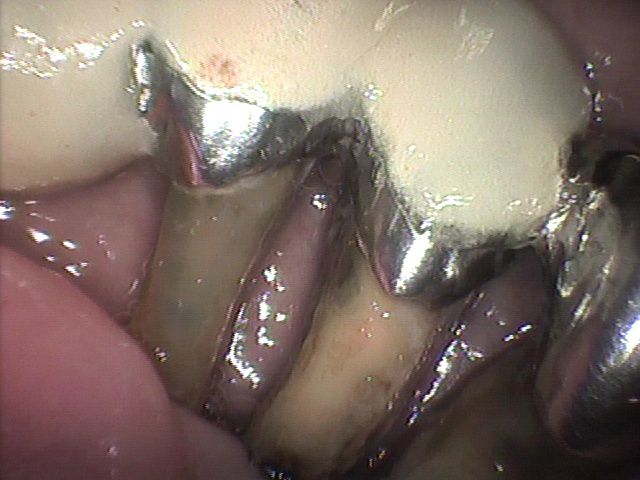

計測データがあれば効果的な咬合圧の負担軽減法を客観的に選択することが可能になります。さらに、選択された治療法の術前、術後の負担軽減効果を評価することもできます。負担軽減法は咬合調整からスプリント(副木)を装着する方法まで色々あります。動揺歯の周囲の歯を含めてスプリント(副木)を装着する方法は最も効果的な負担軽減法です。この治療法は歯の動揺が停止するだけでなく歯周組織の破壊も改善します。7-6(Photo-1~Photo-3)

With measurement data, it becomes possible to objectively select effective occlusion pressure burden reduction method.In addition, it is possible to evaluate the effect of reducing the burden of preoperative and postoperative burden of the selected therapy. There are various ways to reduce burden from occlusal adjustment to a method of installing a splint. The method of attaching the splint including the teeth around the loose tooth is the most effective way of reducing the burden. This treatment not only stops tooth oscillation but also improves periodontal tissue destruction. 7-6(Photo-1~Photo-3)

その結果、1本の歯が傾きますと両隣の歯だけでなく対合歯にも影響が波及し歯並びの乱れが目立つようになります(Photo-1)また前歯では反っ歯になり口を閉じて歯が見えるようになります(Photo-2)